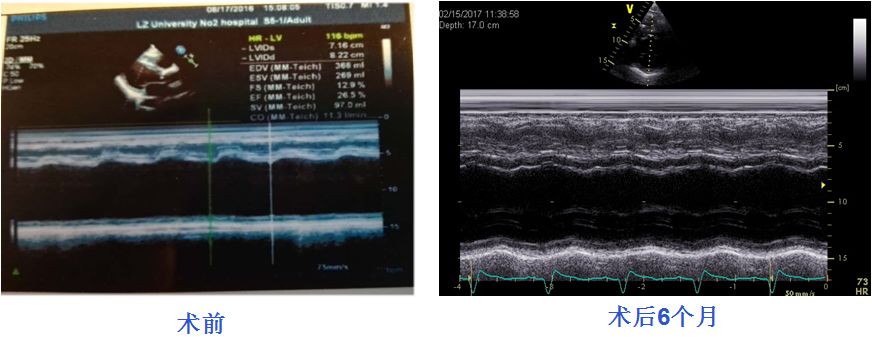

超声心动图评价CRT效果

术前:QRS宽度平均160ms降至120ms

术前超声评估、术后CRT效果评估为患者提供精准个体化的治疗